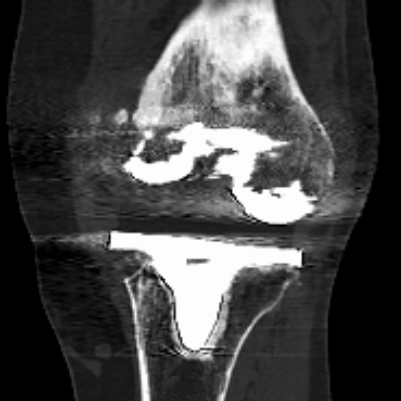

▲CT提示:假体松动,

内侧股骨髁、内侧胫骨平台骨缺损严重